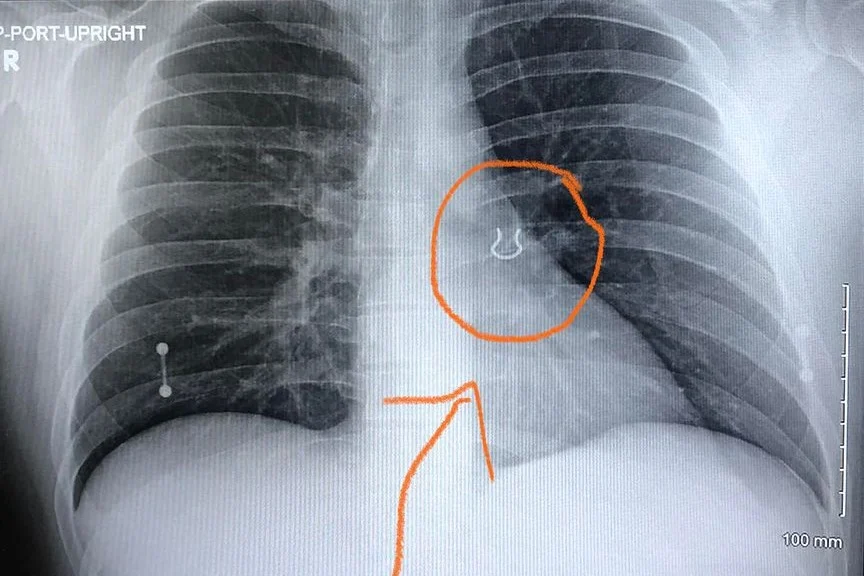

Em um relato feito nas redes sociais, o jardineiro Joey Lykins, 35 anos, conta uma situação inusitada que viveu no último mês. O americano foi socorrido após sofrer uma crise de tosse severa seguida de falta de ar, em um quadro semelhante ao de uma pneumonia. Ao chegar ao pronto socorro, descobriu que os sintomas eram provocados, na realidade, por um piercing alojado em seu pulmão há cinco anos.

“Você está brincando comigo? Eu estive procurando por isso!”, disse o jardineiro ao receber as imagens do exame de raio-x.

O paciente contou aos médicos que provavelmente inalou o piercing usado no septo enquanto dormia. Lykins lembra de ter sentido falta da joia ao acordar em uma manhã de 2017. Ele revirou o quarto à procura do item, mas deu o piercing como perdido.

Com as imagens do raio-x, os médicos suspeitaram que a joia se moveu ligeiramente para dentro do pulmão nos últimos anos, provocando só agora a sensação de bloqueio das vias aéreas e tosse aguda. O objeto foi retirado com uma broncoscopia, procedimento feito com um tubo que passa pela garganta normalmente usado para fazer o diagnóstico de infecções ou remover objetos dos pulmões.